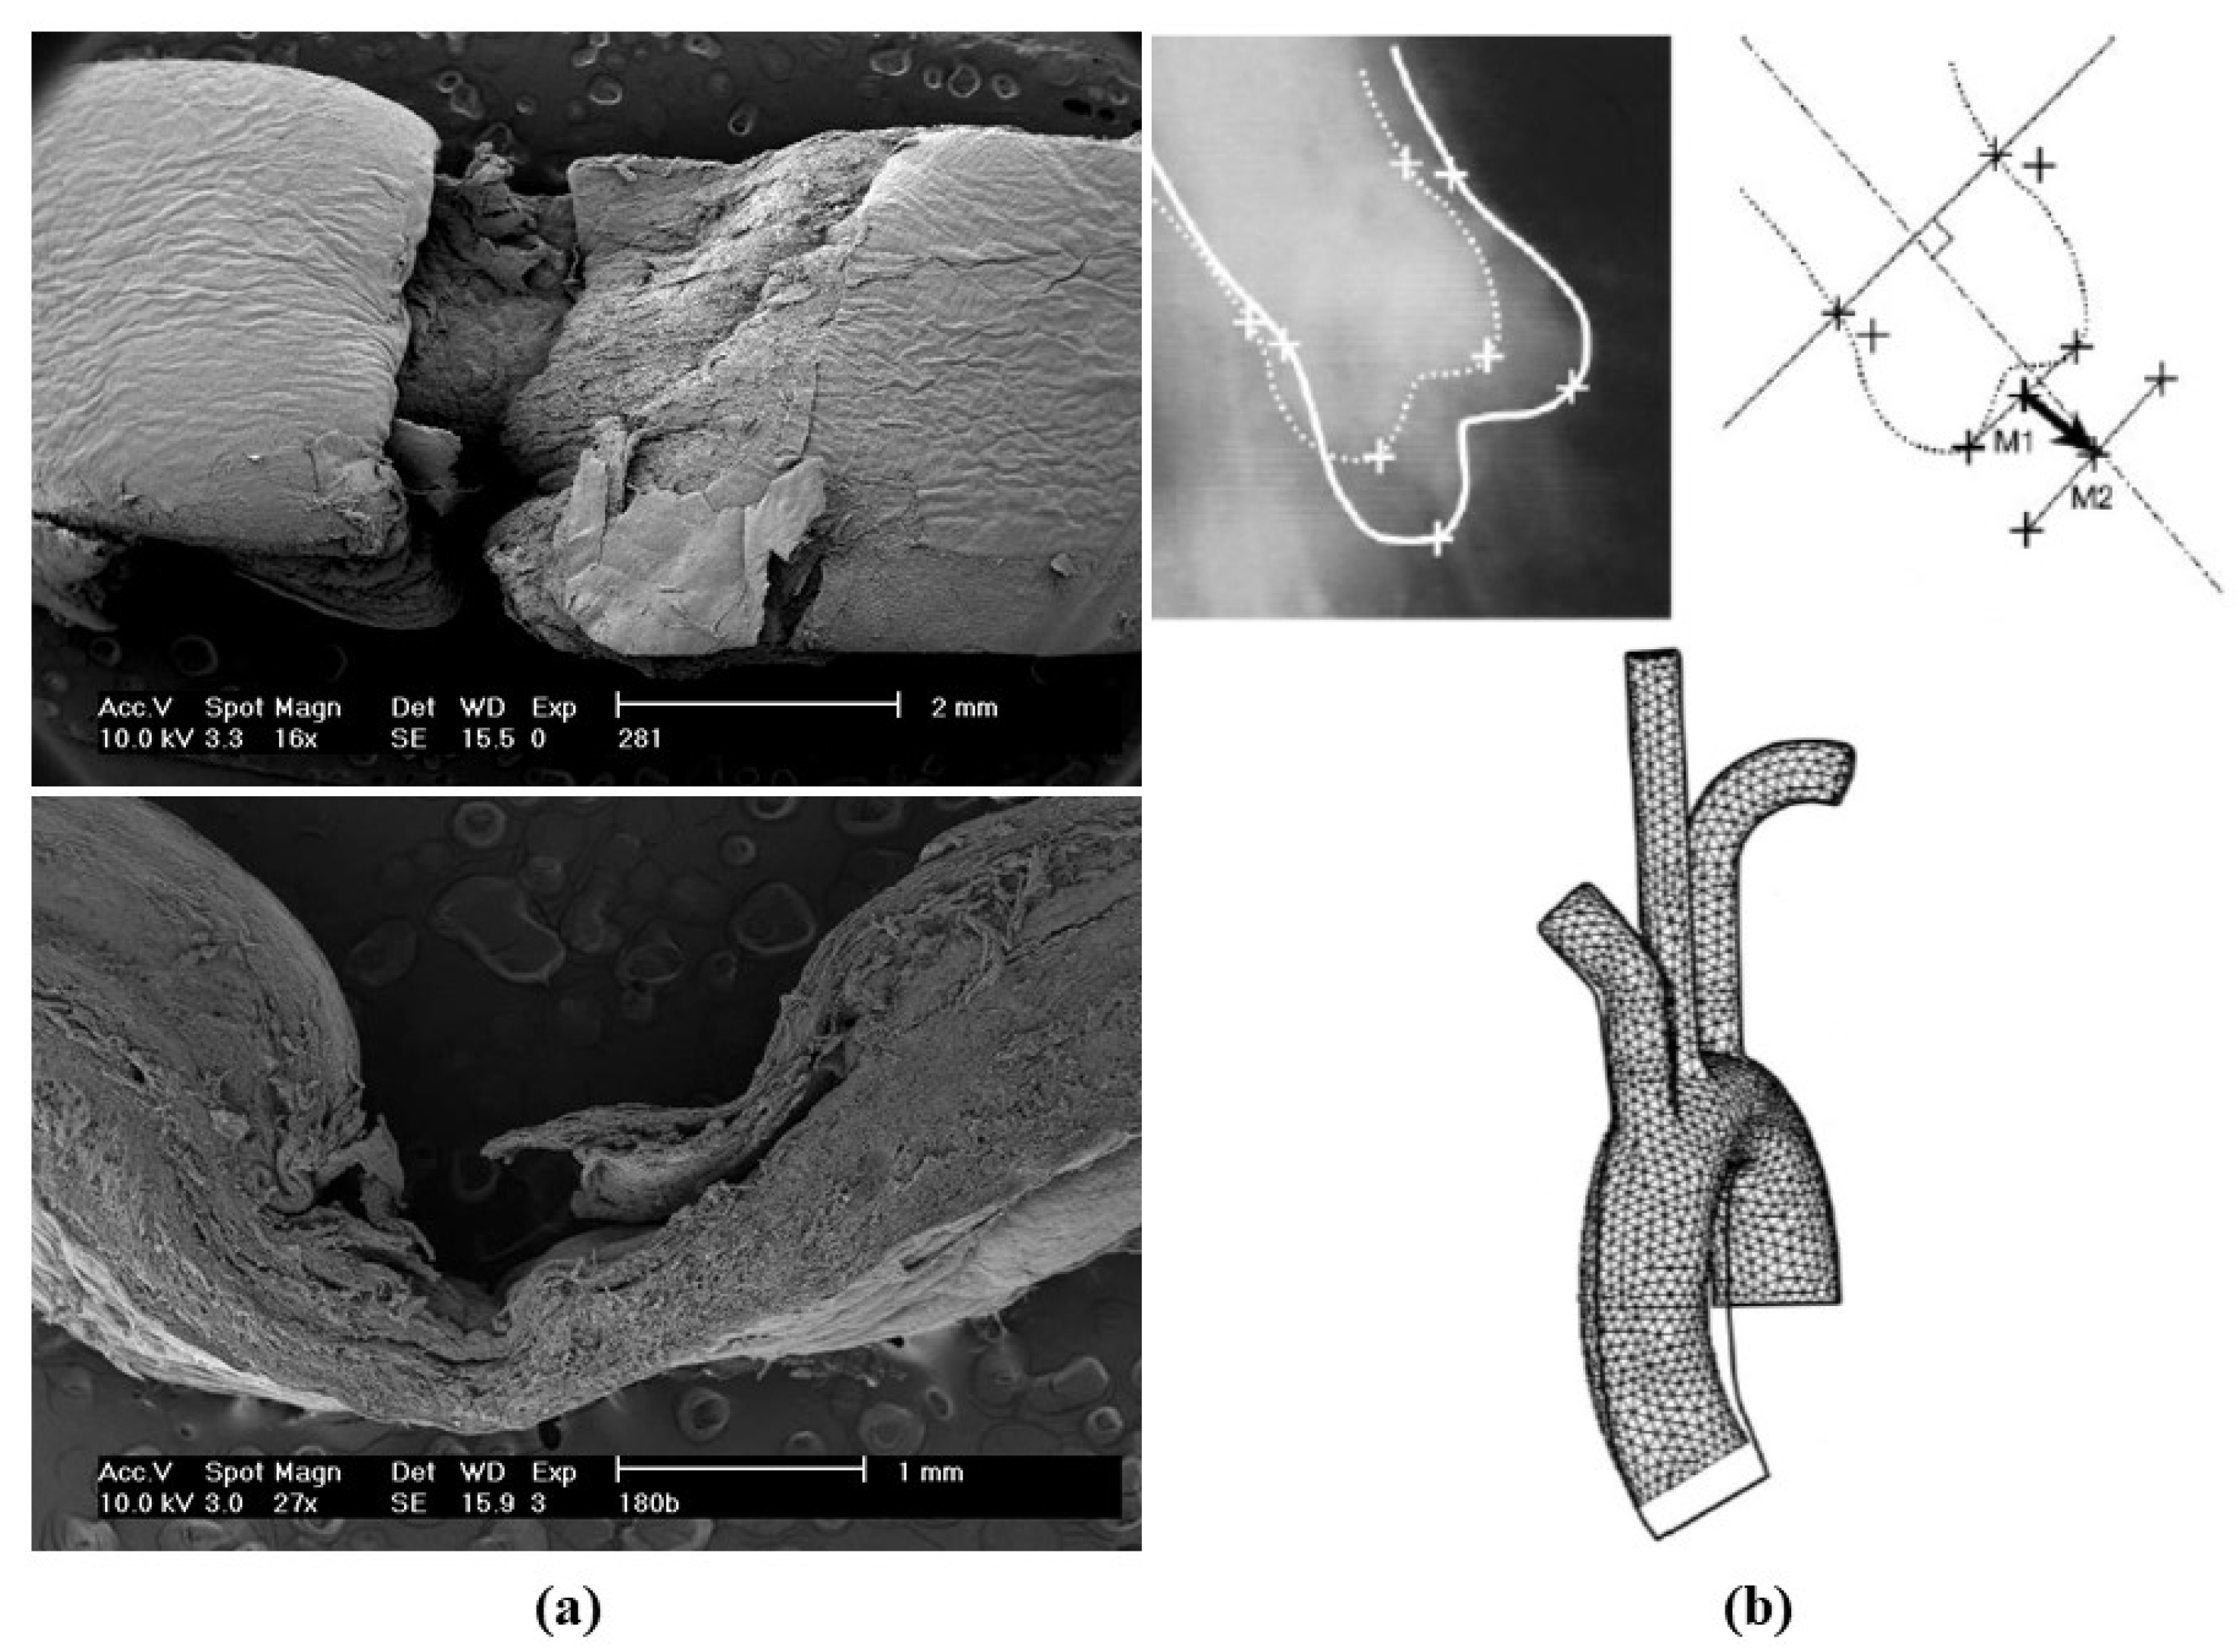

- Decellularization in unimplanted allografts appeared complete, both in the lamellar units of the tunica media and valvular interstitium with disappearance of endothelial lining (Figure 31);

- Cellular repopulation was observed in the outer part of implanted homograft wall by novel smooth muscle cells in the lamellar units (Figure 32a,b) and in the intima with a novel myointimal layer; this layer was noticed also in small animals such as rodents [68]. Novel endothelial cells appeared to line both the aortic wall intima and inflow/outflow at the cusp surface, as well as vasa vasorum, and valve spongiosa appeared repopulated by interstitial cells (Figure 32c,d);

- The ultrastructure of the wall revealed that novel smooth muscle cells have immature aspects, with a central oval nucleus, few contractile filaments and focal densities mainly located close to cytoplasmic membrane and in the paranuclear region; repopulated cells of the cusps are scarcely differentiated cells, in some case showing short intercellular junctions, rough endoplasmic reticulum and focal basal lamina (Figure 33), whereas others exhibited a fibroblast-like morphology;